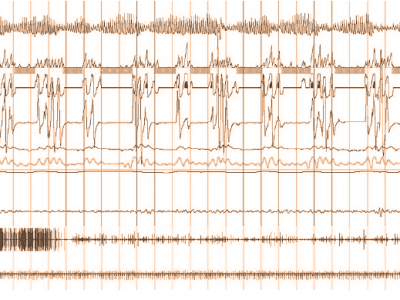

continua a leggerePolisonnografia

La diagnosi dei disturbi del sonno non può prescindere da una valutazione strumentale condotta per l’intera durata della notte…